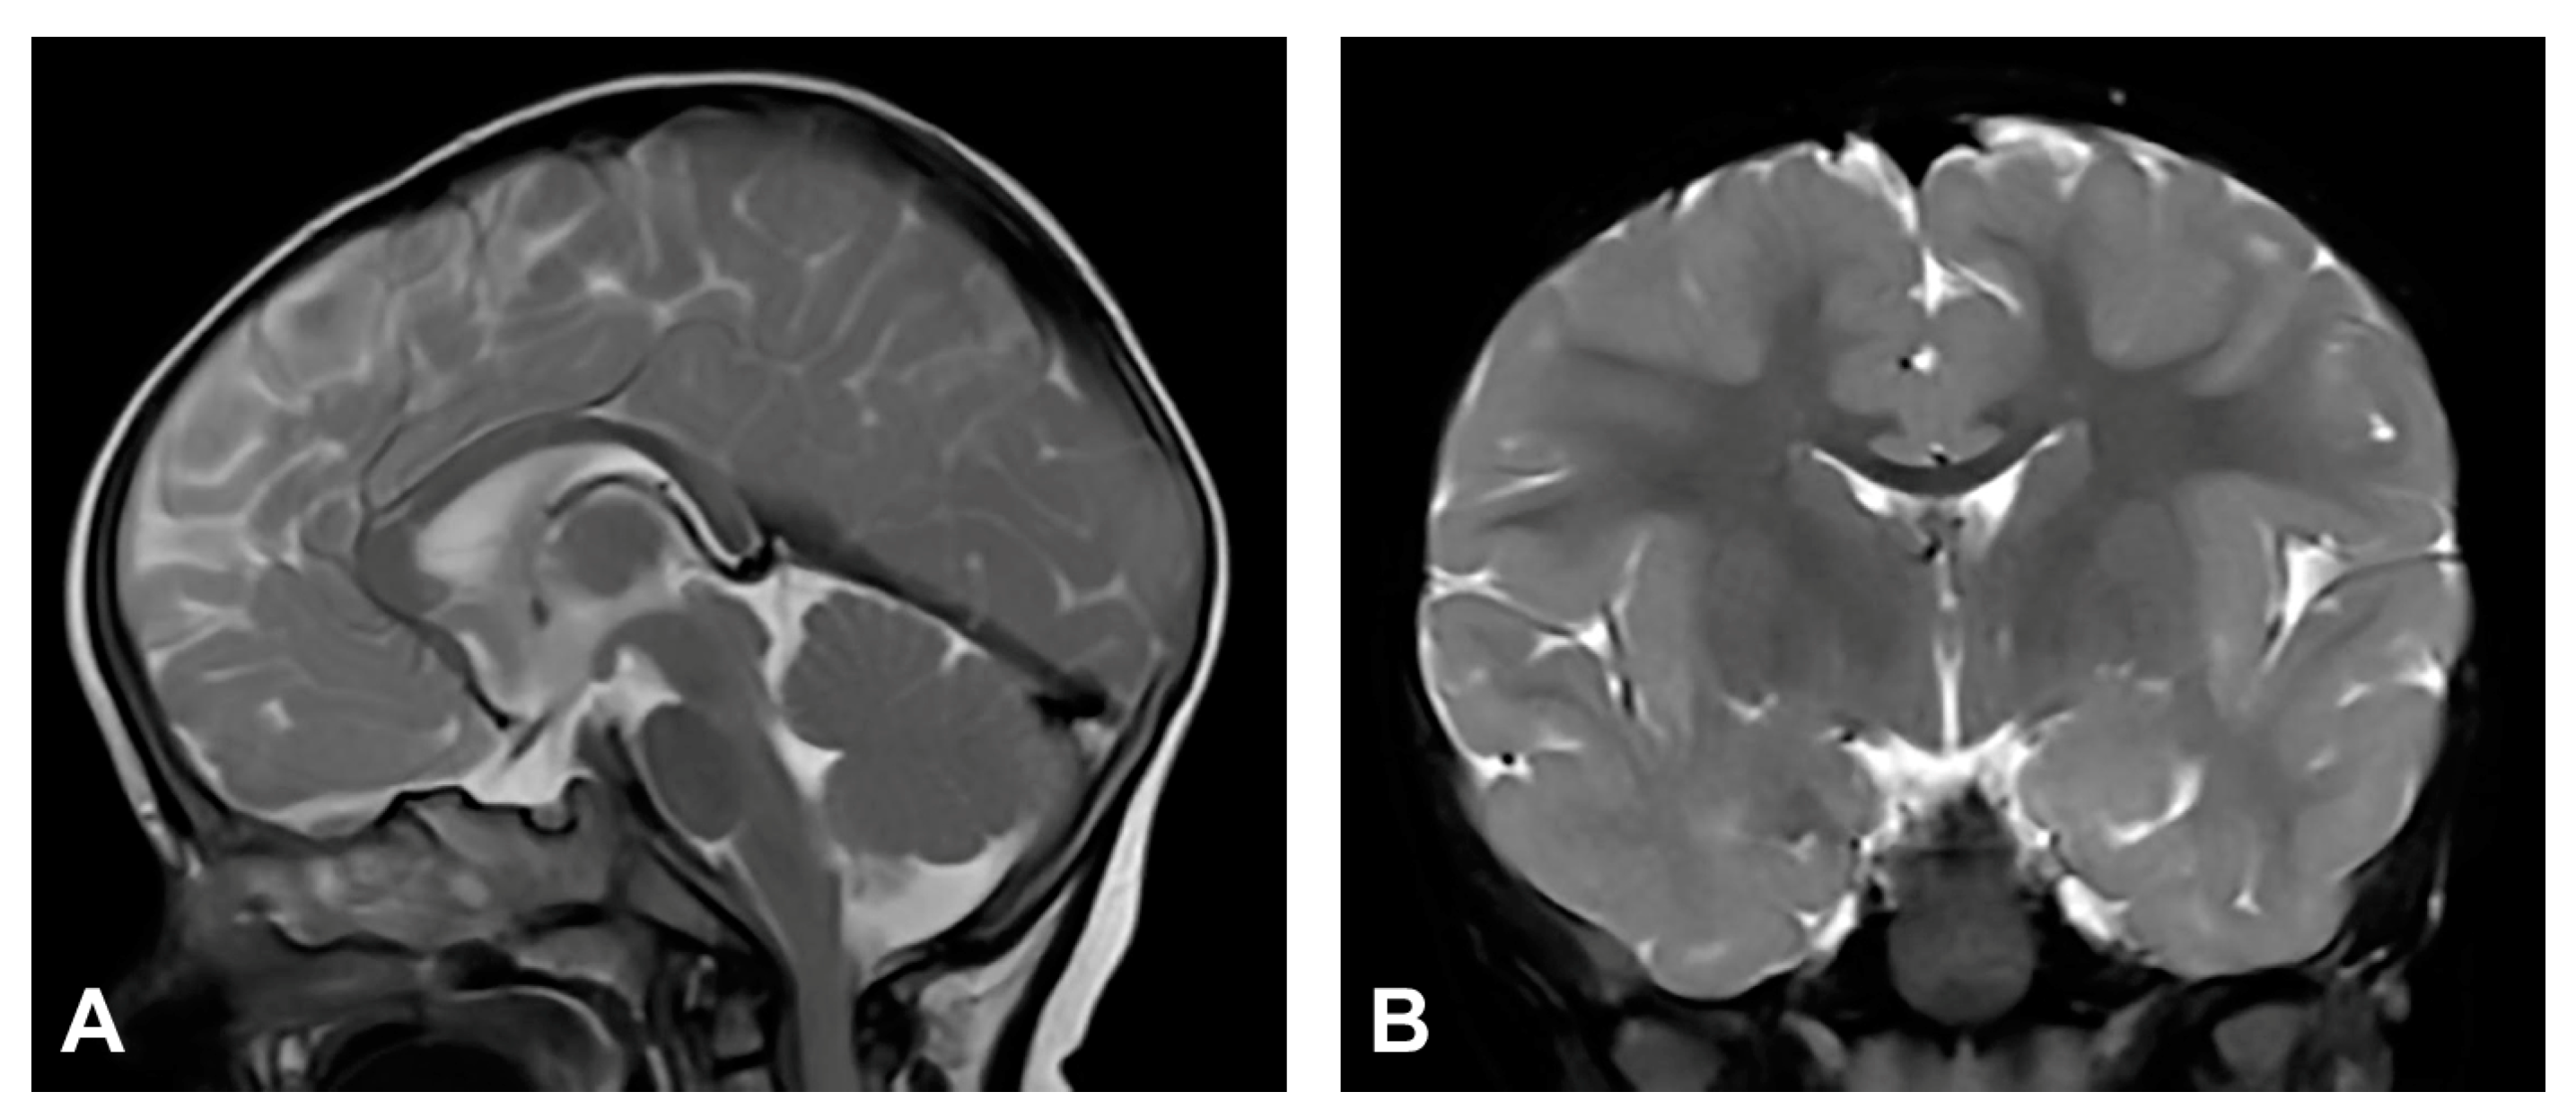

3.2.1. Case 1

3.2.2. Case 2